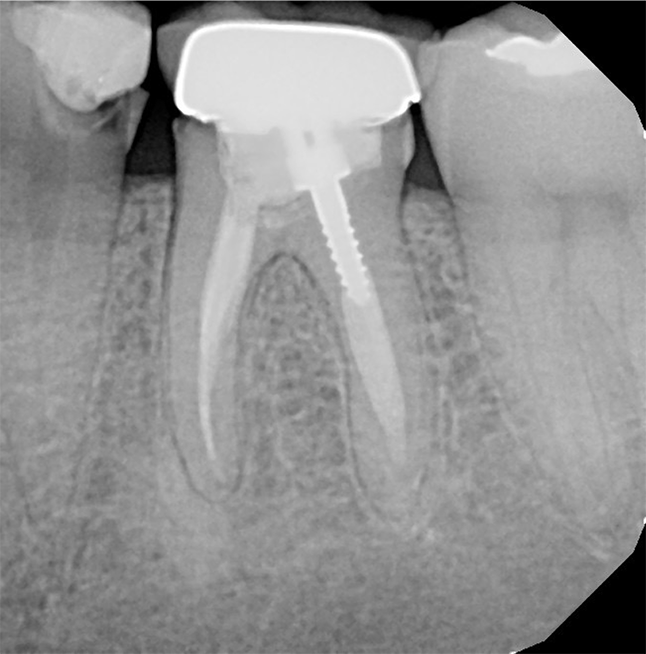

Identium is an excellent choice for implant impressions, multi-unit impressions, impressions where isolation is compromised and impressions with subgingival preps (Fig. 3).

Fig. 3